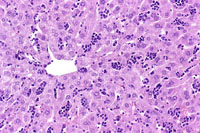

Extramedullary hematopoiesis (EMH) can occur in the liver, especially when there is long-standing anemia. Typical morphological features consist of small aggregates of cells with intensely basophilic nuclei (erythroid) or small collections of immature and mature myelocytic cells (myelopoiesis) located in the sinusoids and, in severe cases, in portal areas.